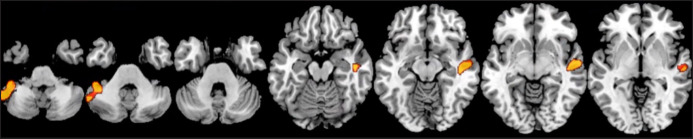

Results: A total of 70 (39 male, 31 female) were analysed, with an average number of occlusal pairs of 10.21 (3.99). According to the Spearman correlation coefficient, a lower number of occlusal pairs was related to a reduction in white matter (right external capsule and posterior limb of the internal capsule), a reduction in grey matter (right temporal superior and medial gyrus and left cerebellum crus 1) and a reduction in thickness of the cerebral cortex (rostral anterior cingulated cortex of the right hemisphere and areas in the right and left hemisphere, especially in the frontal cortex).

Conclusions: The number of occlusal pairs is related to the volume of white matter, grey matter, and thickness of the cerebral cortex in areas of the brain that are directly involved in the onset and progression of Alzheimer's disease and other dementias.